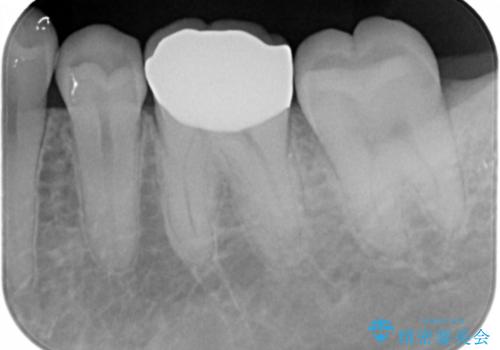

③ジルコニアクラウンで被せる

→欠けた部分をしっかり覆うことができる。薄い歯質の部分がなくなり、歯は割れにくくなる。

ただし、①②よりも歯を大きく削ることになる。

ジルコニアクラウンは白いため、審美性は保たれる。

患者と相談し、金属よりも白いものを入れたい、また、もう歯が欠けてやり直すのは嫌だとのご希望だった。

そのため、歯質の削除量は増えるが、クラウンで被せる③の方針で行くことになった。

- 仮歯・ジルコニアクラウン 12.1万円費用は治療当時の料金となります